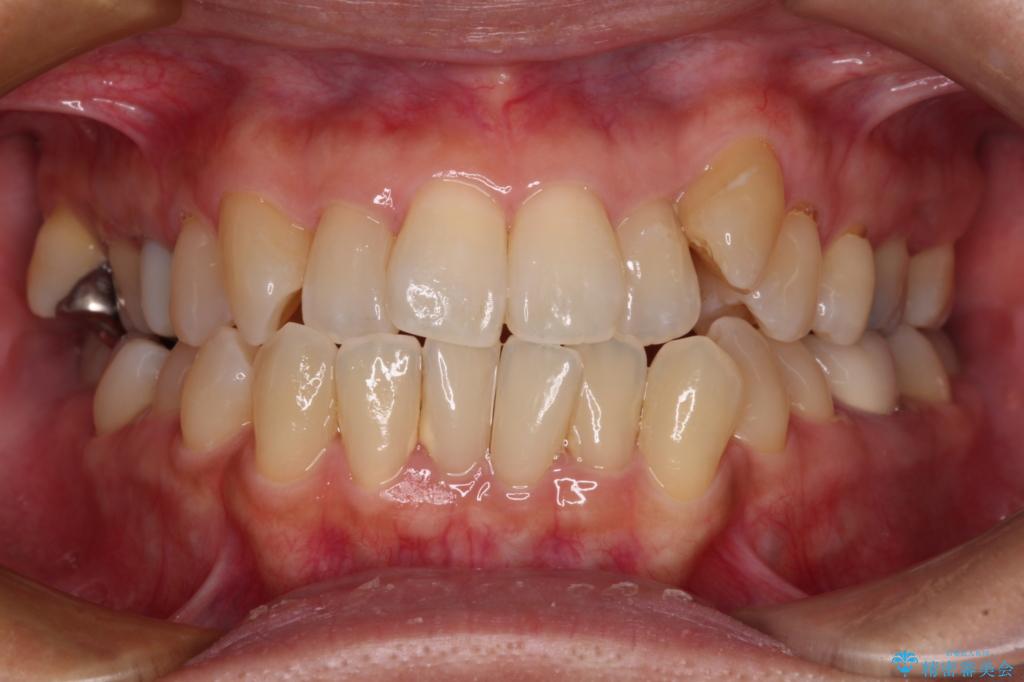

受け口傾向の骨格であり、前歯はクロスバイトまたは切端咬合となっており、下顎を中心に歯列全体の後方移動を行い、IPR(歯と歯の間を削る)によってデコボコが解消するように設計し、インビザラインにより治療を行うこととしました。

受け口傾向のインビザライン矯正は比較的治療を行いやすいため、きれいに仕上げることができました。舌の突出癖が顕著であったため、改善のためのトレーニングをしっかりと行っていただきました。